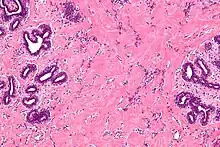

| High magnification micrograph of pseudoangiomatous stromal hyperplasia showing the characteristic small, anastomosing blood vessel-like channels. H&E stain. | |